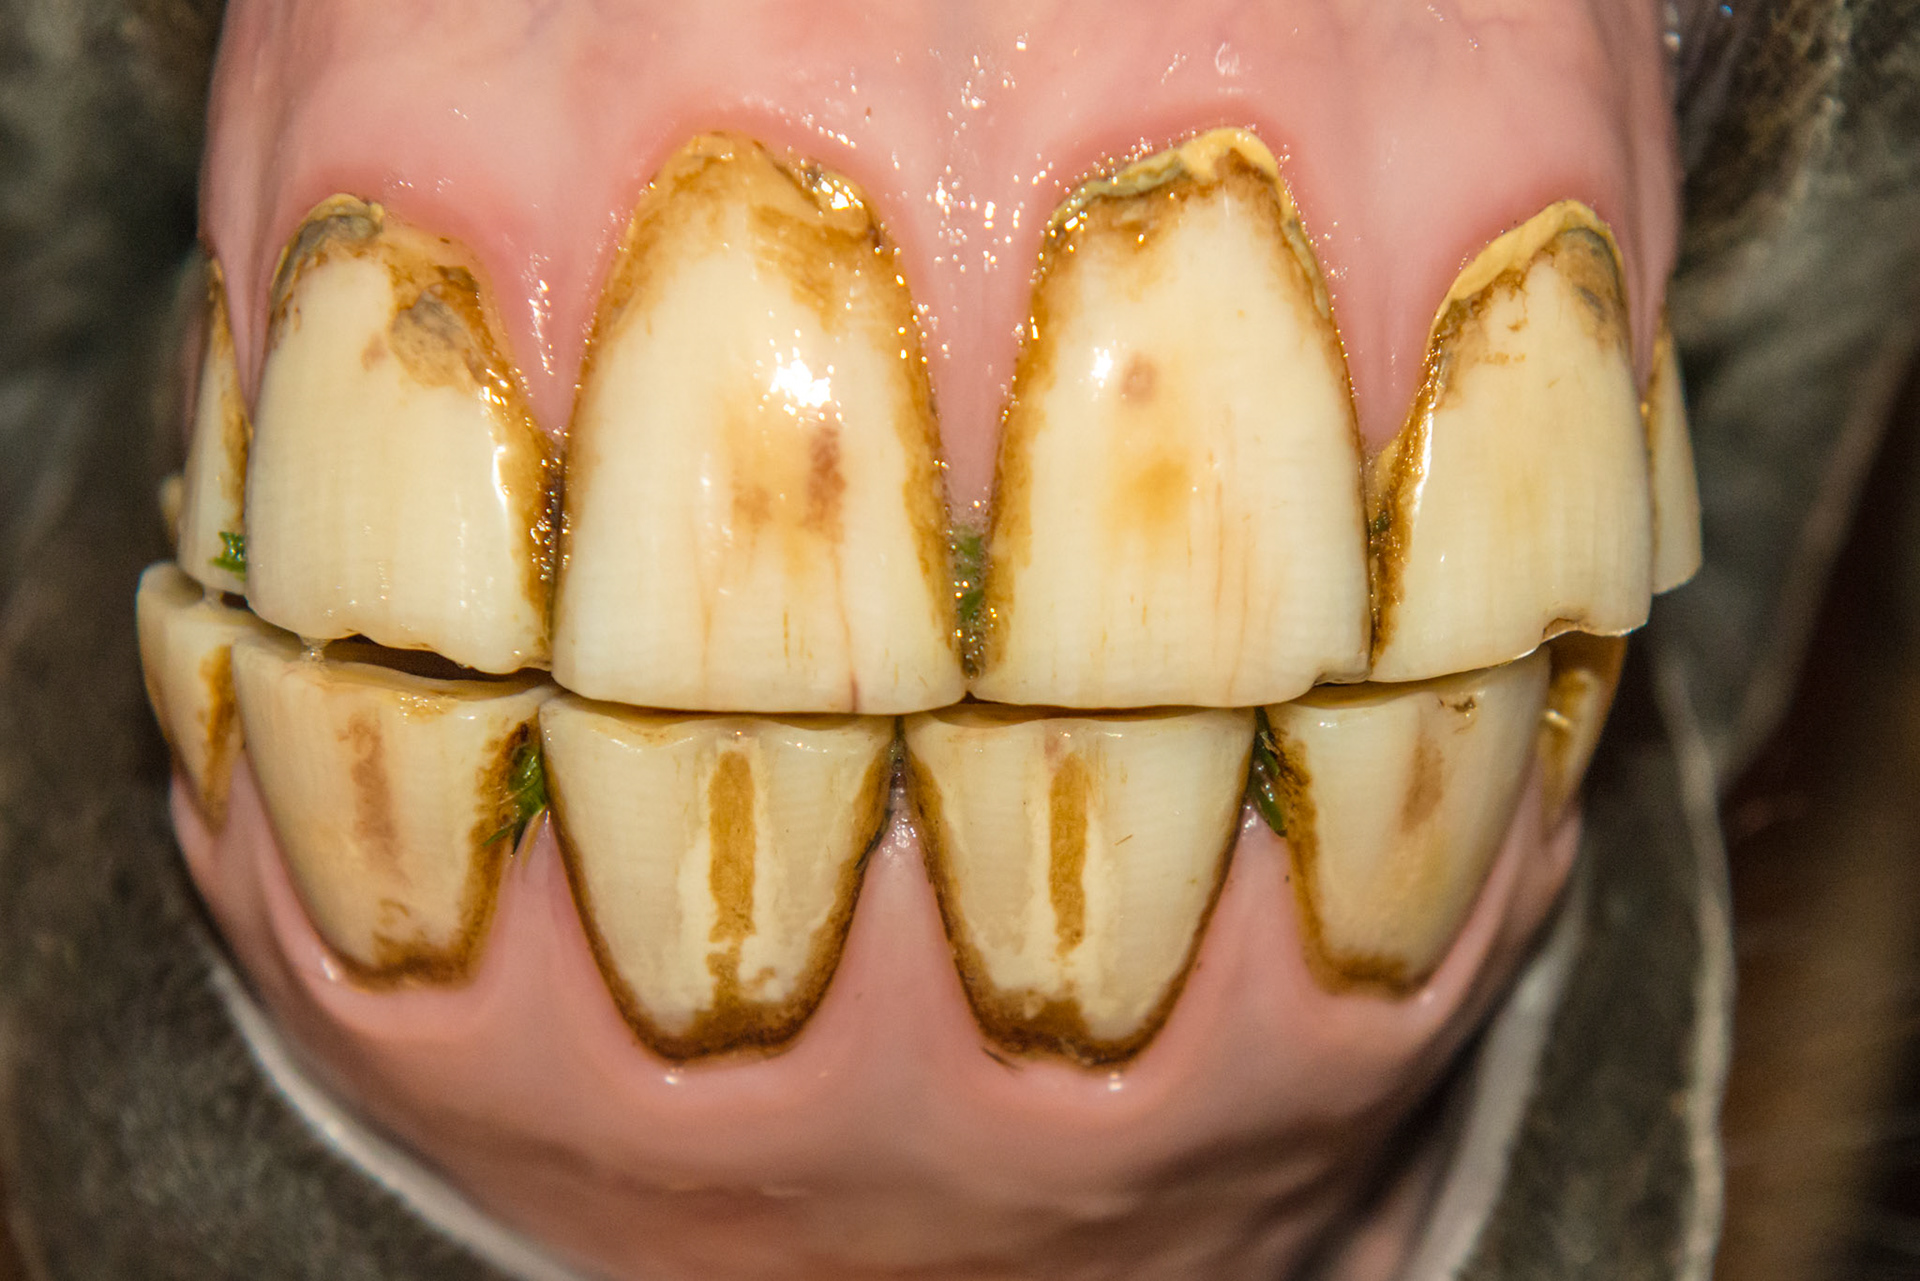

12yr 8mo note EOTRH